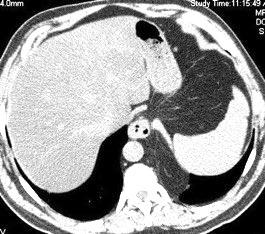

49. INVERSIÓN DIAFRAGMÁTIC. MESOTELIOMA

La ocupación del espacio pleural por derrame (o obstrucción aérea) se acomoda con expansión aumentada de la caja torácica, especialmente en eje vertical. La consecuencia es aplanamiento e incluso inversión diafragmática.

Afzal S, Fatima K, Ambareen M. Antenatal ultrasound diagnosis of congenital high airway obstruction syndrome: a case report and review of literature. Cureus. 2019. Thoma R et al. Physiology of breathlessness associated with pleural effusions. Curr Opin Pulm Med. 2015

Wang JS et al. Changes in pulmonary mechanics and gas exchange after thoracentesis on patients with inversion of a hemidiaphragm secondary to large pleural effusion . Chest 1995

Mesotelioma epitelioide